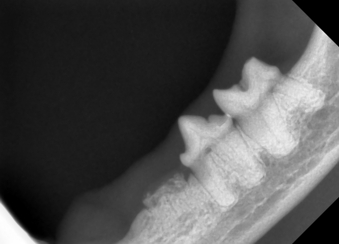

Feline Tooth Resorption

- Dental Radiology